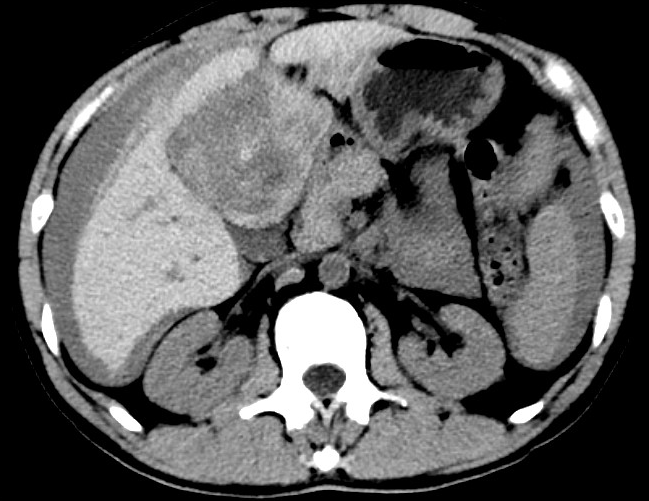

放下電話的白葦急赴消內(nèi)三搶救室會診,經(jīng)仔細(xì)查體、對患者腹部CT進(jìn)行詳細(xì)閱片、綜合評估患者后,考慮患者是肝占位破裂出血?;颊卟∏槭志o急、一刻也不容耽誤,需立刻急診行肝動脈造影 栓塞術(shù)進(jìn)行止血治療,在與患者家屬溝通后,立即通知消化介入室準(zhǔn)備急診手術(shù)。

入手術(shù)室時,患者神志迷糊,口唇干燥、重度貧血貌,心電監(jiān)護(hù)提示:心率140-160次/分,血壓70/43mmHg,這是失血性休克的表現(xiàn)!白葦快速建立靜脈通道緊急給予輸血,升壓,止血等液,立即給予肝動脈造影,術(shù)中發(fā)現(xiàn)肝左葉疑似腫瘤病灶、病灶周圍血管分支有造影劑外溢,考慮血管破裂出血,迅速給予栓塞微球進(jìn)行肝動脈栓塞。整個手術(shù)過程不足20分鐘,術(shù)后即刻患者心率降至100-110次/分、血壓升至90/60mmHg。

術(shù)后給予積極抗炎,止血,保肝、利尿等對癥治療,復(fù)查血常規(guī)提示活動性出血停止后,在超聲引導(dǎo)下行腹腔穿刺引流術(shù),術(shù)后3天共引流出血性腹水約4000ml?;颊呓?jīng)復(fù)查各項指標(biāo)均趨于正常,復(fù)查CT提示腹腔積血已基本吸收,患者康復(fù)出院。